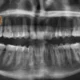

Panoramic X-rays: The Standard Tool

Panoramic x-rays create a single, flat image showing your entire jaw—all teeth, sinuses, and bone structure in one view.

For wisdom teeth, panoramic x-rays show:

- Whether wisdom teeth exist and their general position

- Approximate nerve canal location

- General proximity of roots to nerve

- Whether infection or cysts are present